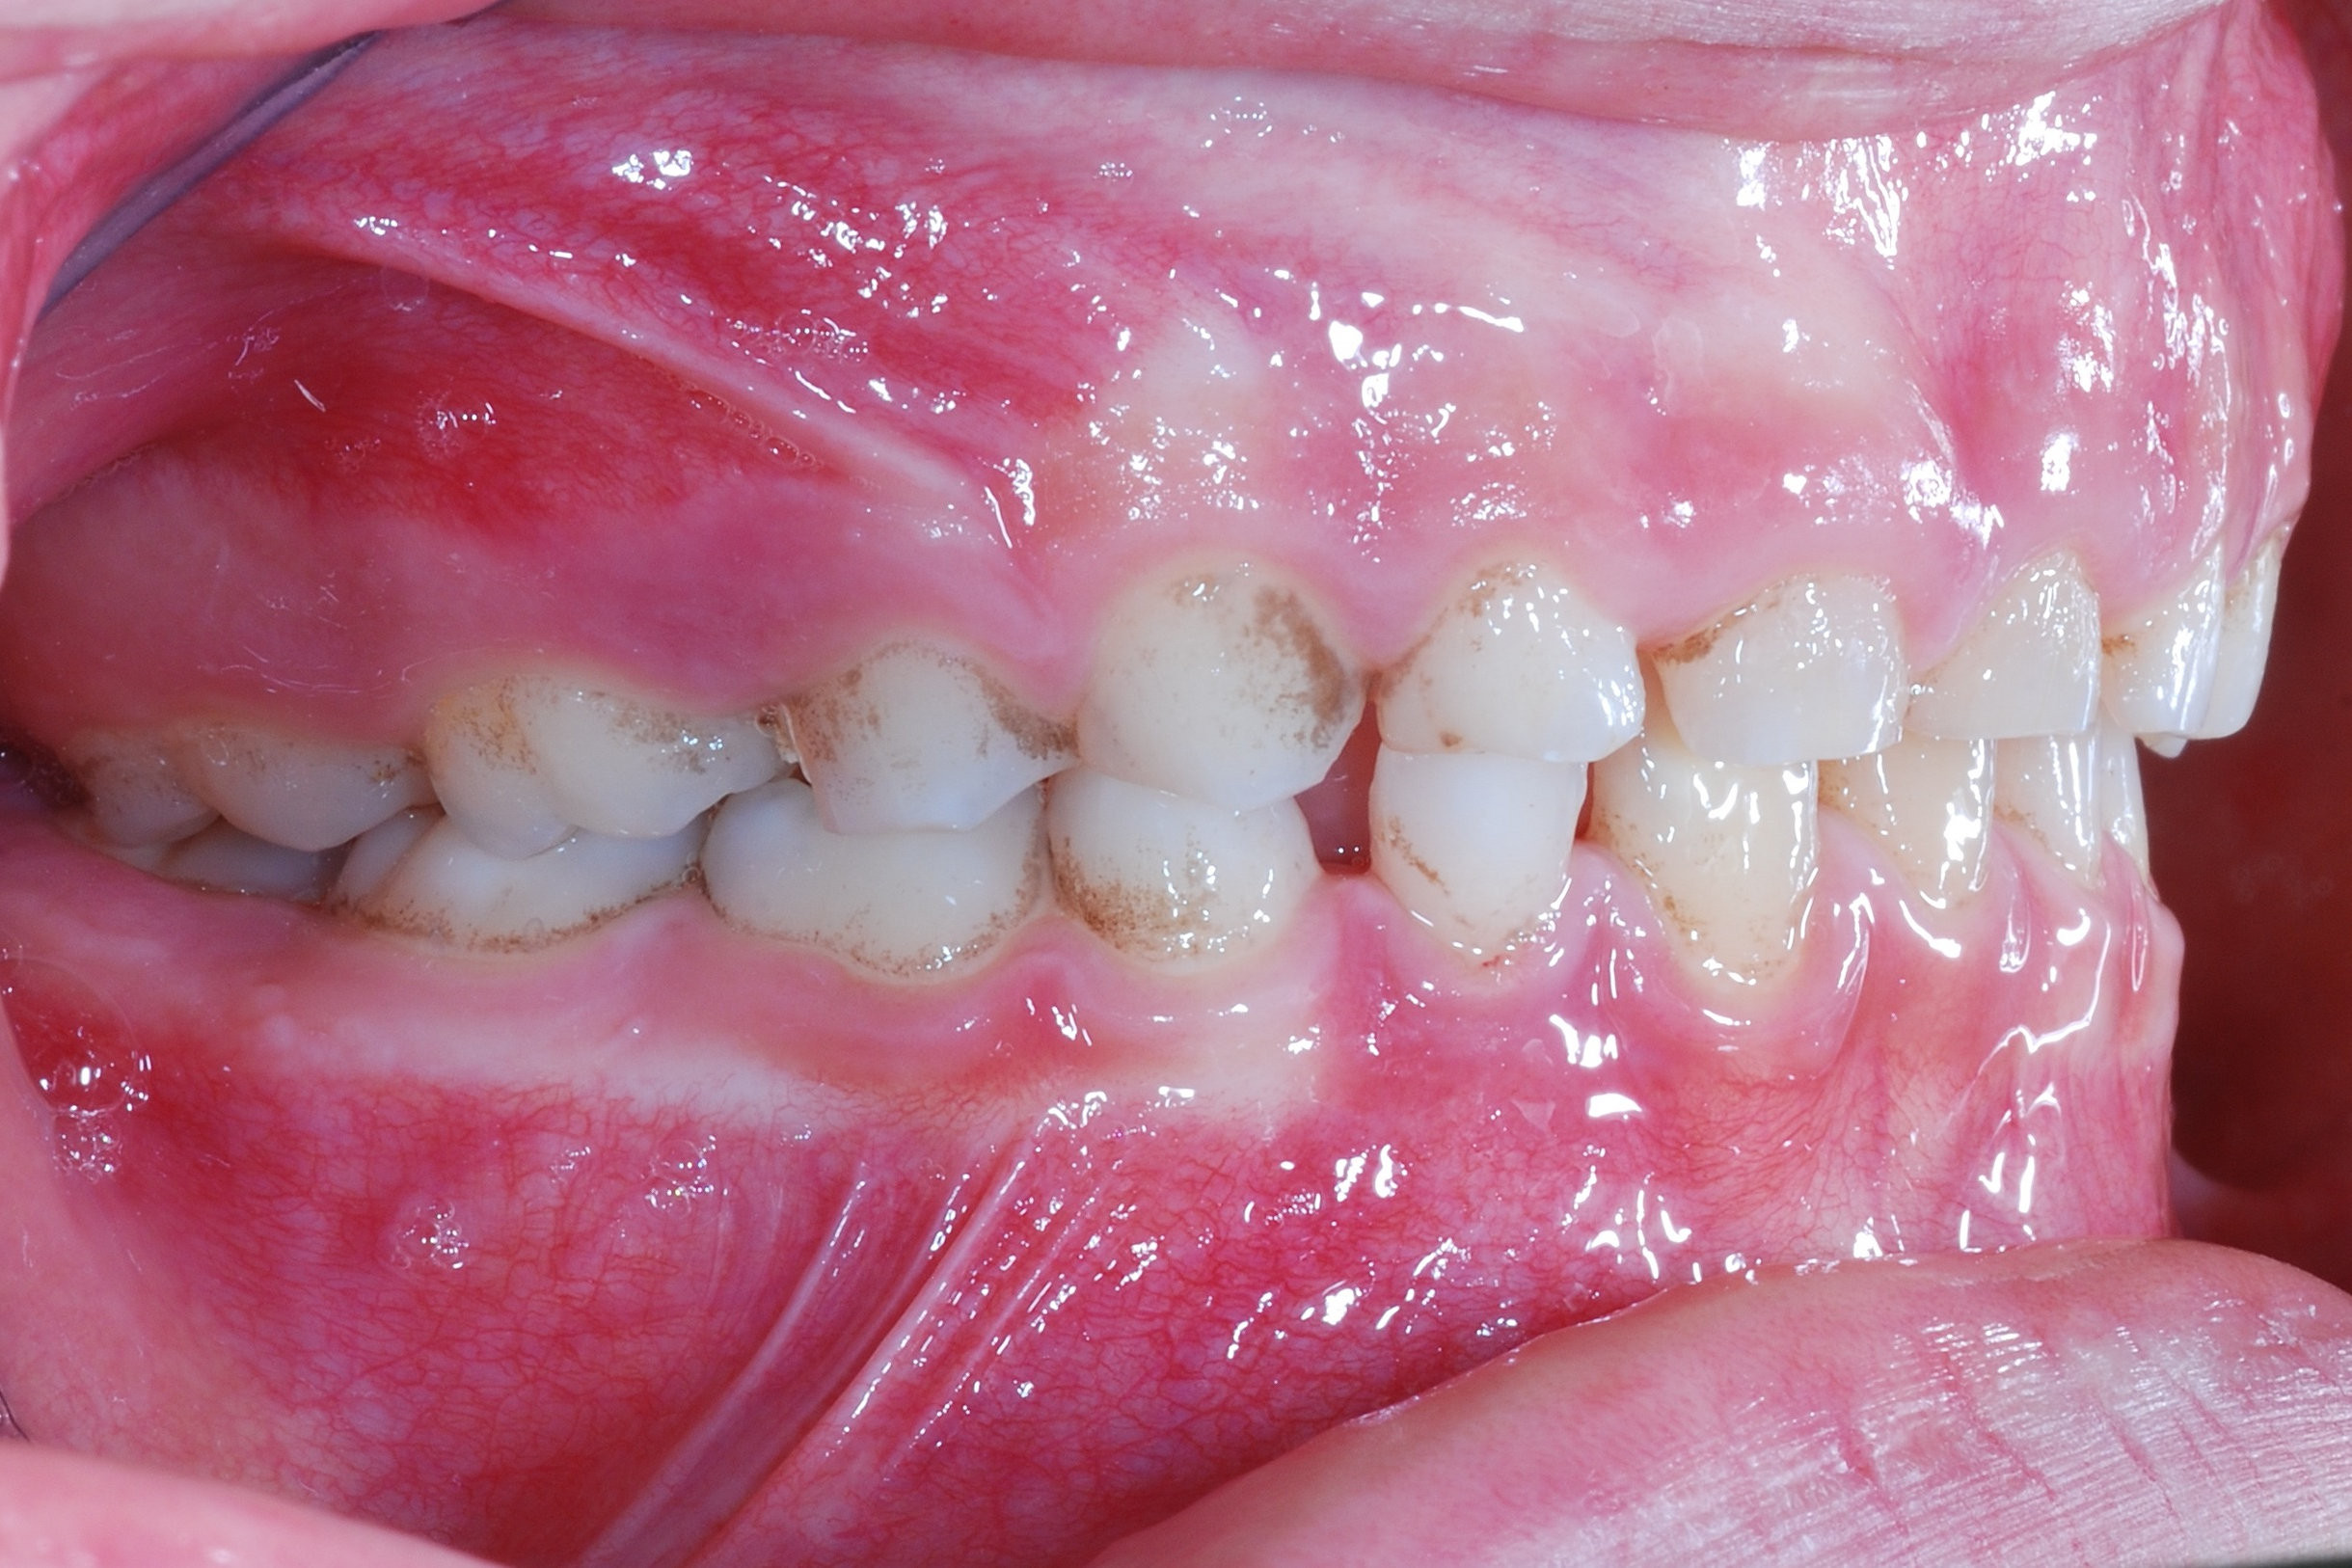

Infine, le black stain sono delle macchioline o linee di colore nero o bluastro che formano un orlo scuro sulla zona del colletto dentale (la parte più vicina alla gengiva). Queste pigmentazioni batteriche possono comparire sia sui denti da latte che su quelli permanenti, ma in genere sono più frequenti nel primo caso, e tendono a scomparire con lo sviluppo e l’età adulta.

Queste macchie nere sui denti sono dovute alla presenza di batteri cromogeni in grado di secernere delle sostanze a base di zolfo, che a loro volta vanno a formare un composto insolubile con il ferro normalmente presente nella bocca. Tale composto pigmenta di nero la superficie dei denti e, pur non essendo dannoso, risulta di difficile rimozione con la pulizia quotidiana. Le black stain inoltre tendono a riformarsi anche dopo una sessione di igiene orale dal dentista, seppure in forma più lieve.

Per questo è indicato sottoporsi a delle sedute periodiche di pulizia, in cui l’odontoiatra procederà con la rimozione delle macchie mediante l’applicazione di un protocollo specifico. Sarà inoltre essenziale adottare una scrupolosa igiene dentale domiciliare e alcune manovre preventive allo scopo di mantenere i risultati ottenuti dal dentista.